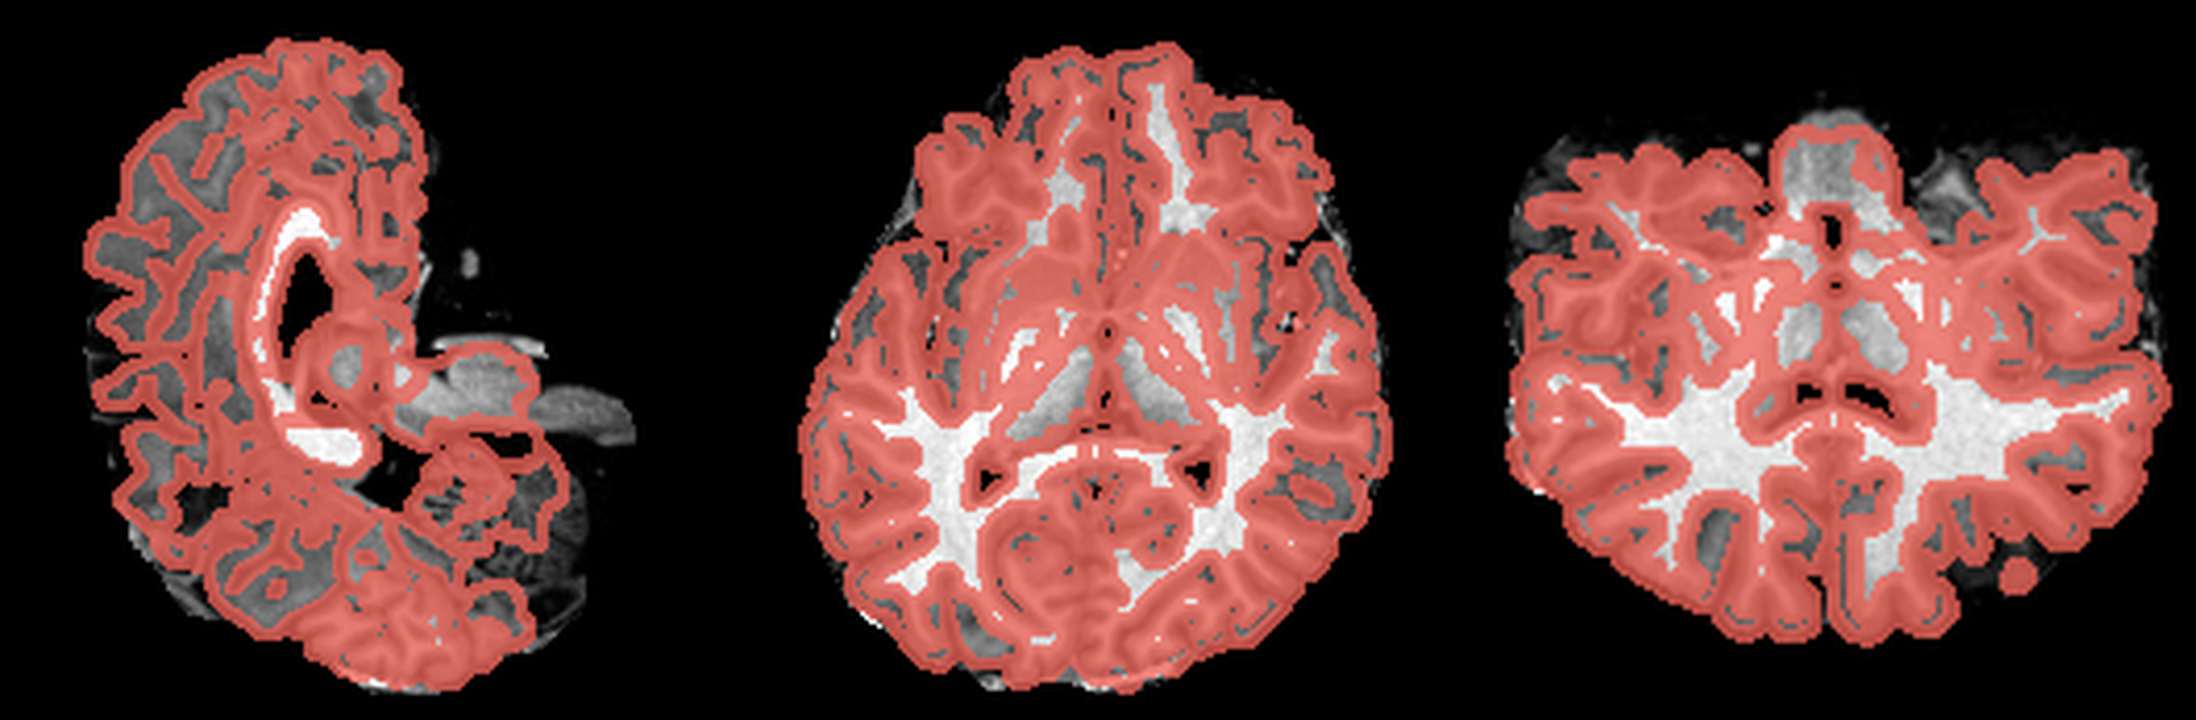

After the four-hour analysis, FreeSurfer had already given me what I needed to inspect the scan: a segmented volume that could be overlaid directly on the anatomical MRI. Visualising that (using a tool like ITK-SNAP), I got something a bit more interpretable than the original slices:

These are three orthogonal slices of my brain, with borders drawn around FreeSurfer’s own segmentations.